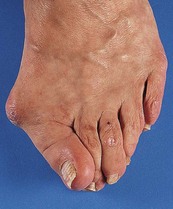

Site: Determine whether the pain originates from a joint (arthralgia) (Box 14.1), muscle (myalgia) or other soft tissue. The site may be well localised and suggest the diagnosis, e.g. the first metatarsophalangeal joint in gout (Fig. 14.2), or in several joints suggesting an inflammatory arthritis.

Fig. 14.2 Acute gout of the first metatarsophalangeal joint. This causes swelling, erythema, and extreme pain and tenderness (podagra).

Gout of the first MTP joint causes marked redness and soft-tissue swelling. This is followed by peeling of the superficial skin and pain on movement or touch.